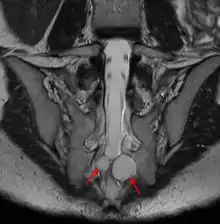

| MRI image showing a Tarlov cyst | |

Tarlov cysts, are type II innervated meningeal cysts, cerebrospinal-fluid-filled (CSF) sacs most frequently located in the spinal canal of the sacral region of the spinal cord (S1–S5) and much less often in the cervical, thoracic or lumbar spine. They can be distinguished from other meningeal cysts by their nerve-fiber-filled walls. Tarlov cysts are defined as cysts formed within the nerve-root sheath at the dorsal root ganglion.[2] The etiology of these cysts is not well understood; some current theories explaining this phenomenon have not yet been tested or challenged but include increased pressure in CSF, filling of congenital cysts with one-way valves, inflammation in response to trauma and disease. They are named for American neurosurgeon Isadore Tarlov, who described them in 1938.[3]

Tarlov cysts are relatively uncommon when compared to other neurological cysts. Initially, Isadore Tarlov believed them to be asymptomatic, however as his research progressed, Tarlov found them to be symptomatic in a number of patients. These cysts are often detected incidentally during MRI or CT scans for other medical conditions. They are also observed using magnetic resonance neurography with communicating subarachnoid cysts of the spinal meninges. Cysts with diameters of 1 cm or larger are more likely to be symptomatic; although cysts of any size may be symptomatic dependent on location and etiology. Some 40% of patients with symptomatic Tarlov cysts can associate a history of trauma or childbirth.[4] Current treatment options include CSF aspiration, fibrin-glue therapy, laminectomy with wrapping of the cyst, among other surgical treatment approaches. Interventional treatment of Tarlov cysts is the only means by which symptoms might permanently be resolved due to the fact that the cysts often refill after aspiration. Tarlov cysts often enlarge over time, especially if the sac has a check valve type opening. They are differentiated from other meningeal and arachnoid cysts because they are innervated and diagnosis can in cases be demonstrated with subarachnoid communication.

Both CT and MRI are good imaging procedures that allow the detection of extradural spinal masses such as Tarlov cysts. Magnetic resonance neurography is an emerging imaging technology based on MRI that highlights neurologic tissue. Often cysts are under reported and under diagnosed as radiologists and neurosurgeons have been traditionally taught to ignore these cysts. Patients frequently experience difficulty in diagnosis, however this is changing as Tarlov cysts have now been recognized by NORD as a rare disease.[16]

MRI

MRI, or Magnetic Resonance Imaging, is considered the imaging study of choice in identifying Tarlov cysts. MRI provides better resolution of tissue density, absence of bone interference, multiplanar capabilities, and is noninvasive. Plain films may show bony erosion of the spinal canal or of the sacral foramina. On MRI pictures, the signal is the same as the CSF one.